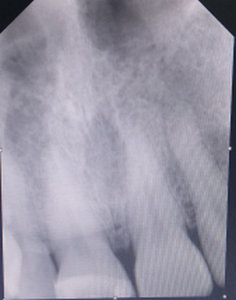

Вчера был у стоматолога, делали снимок, на снимке сказали с зубом все хорошо и не стали ничего с ним делать, выписали противовоспалительные препараты. Сказали, если до понедельника боль не пройдёт, будут удалять пломбу. Боль не проходит, отдаёт в щеку. За день до того как заболел зуб, пил холодную воду. Зуб шестёрка.

После пломбирования каналов зуба возможно воспаление периодонта, причинами могут быть:

Одним из признаков воспаления периодонта является болезненность при накусывании на зуб.